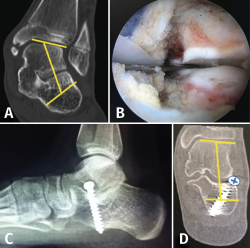

Técnica quirúrgica (Figura 13)

Figura 13. Osteotomía de deslizamiento medial del calcáneo. Escopia intraoperatoria lateral y axial de retropié donde se visualiza la osteotomía de deslizamiento medial del calcáneo.

La osteotomía es perpendicular a la cara lateral del calcáneo y oblicua hacia anterior desde el borde dorsal de la tuberosidad mayor hasta su borde plantar. Aunque clásicamente se realiza esta osteotomía de forma abierta, actualmente se puede realizar de forma percutánea. Mediante maniobra externa realizamos una medialización de al menos 1 cm, más osteosíntesis con AK o tornillos canulados de esponjosa(11).